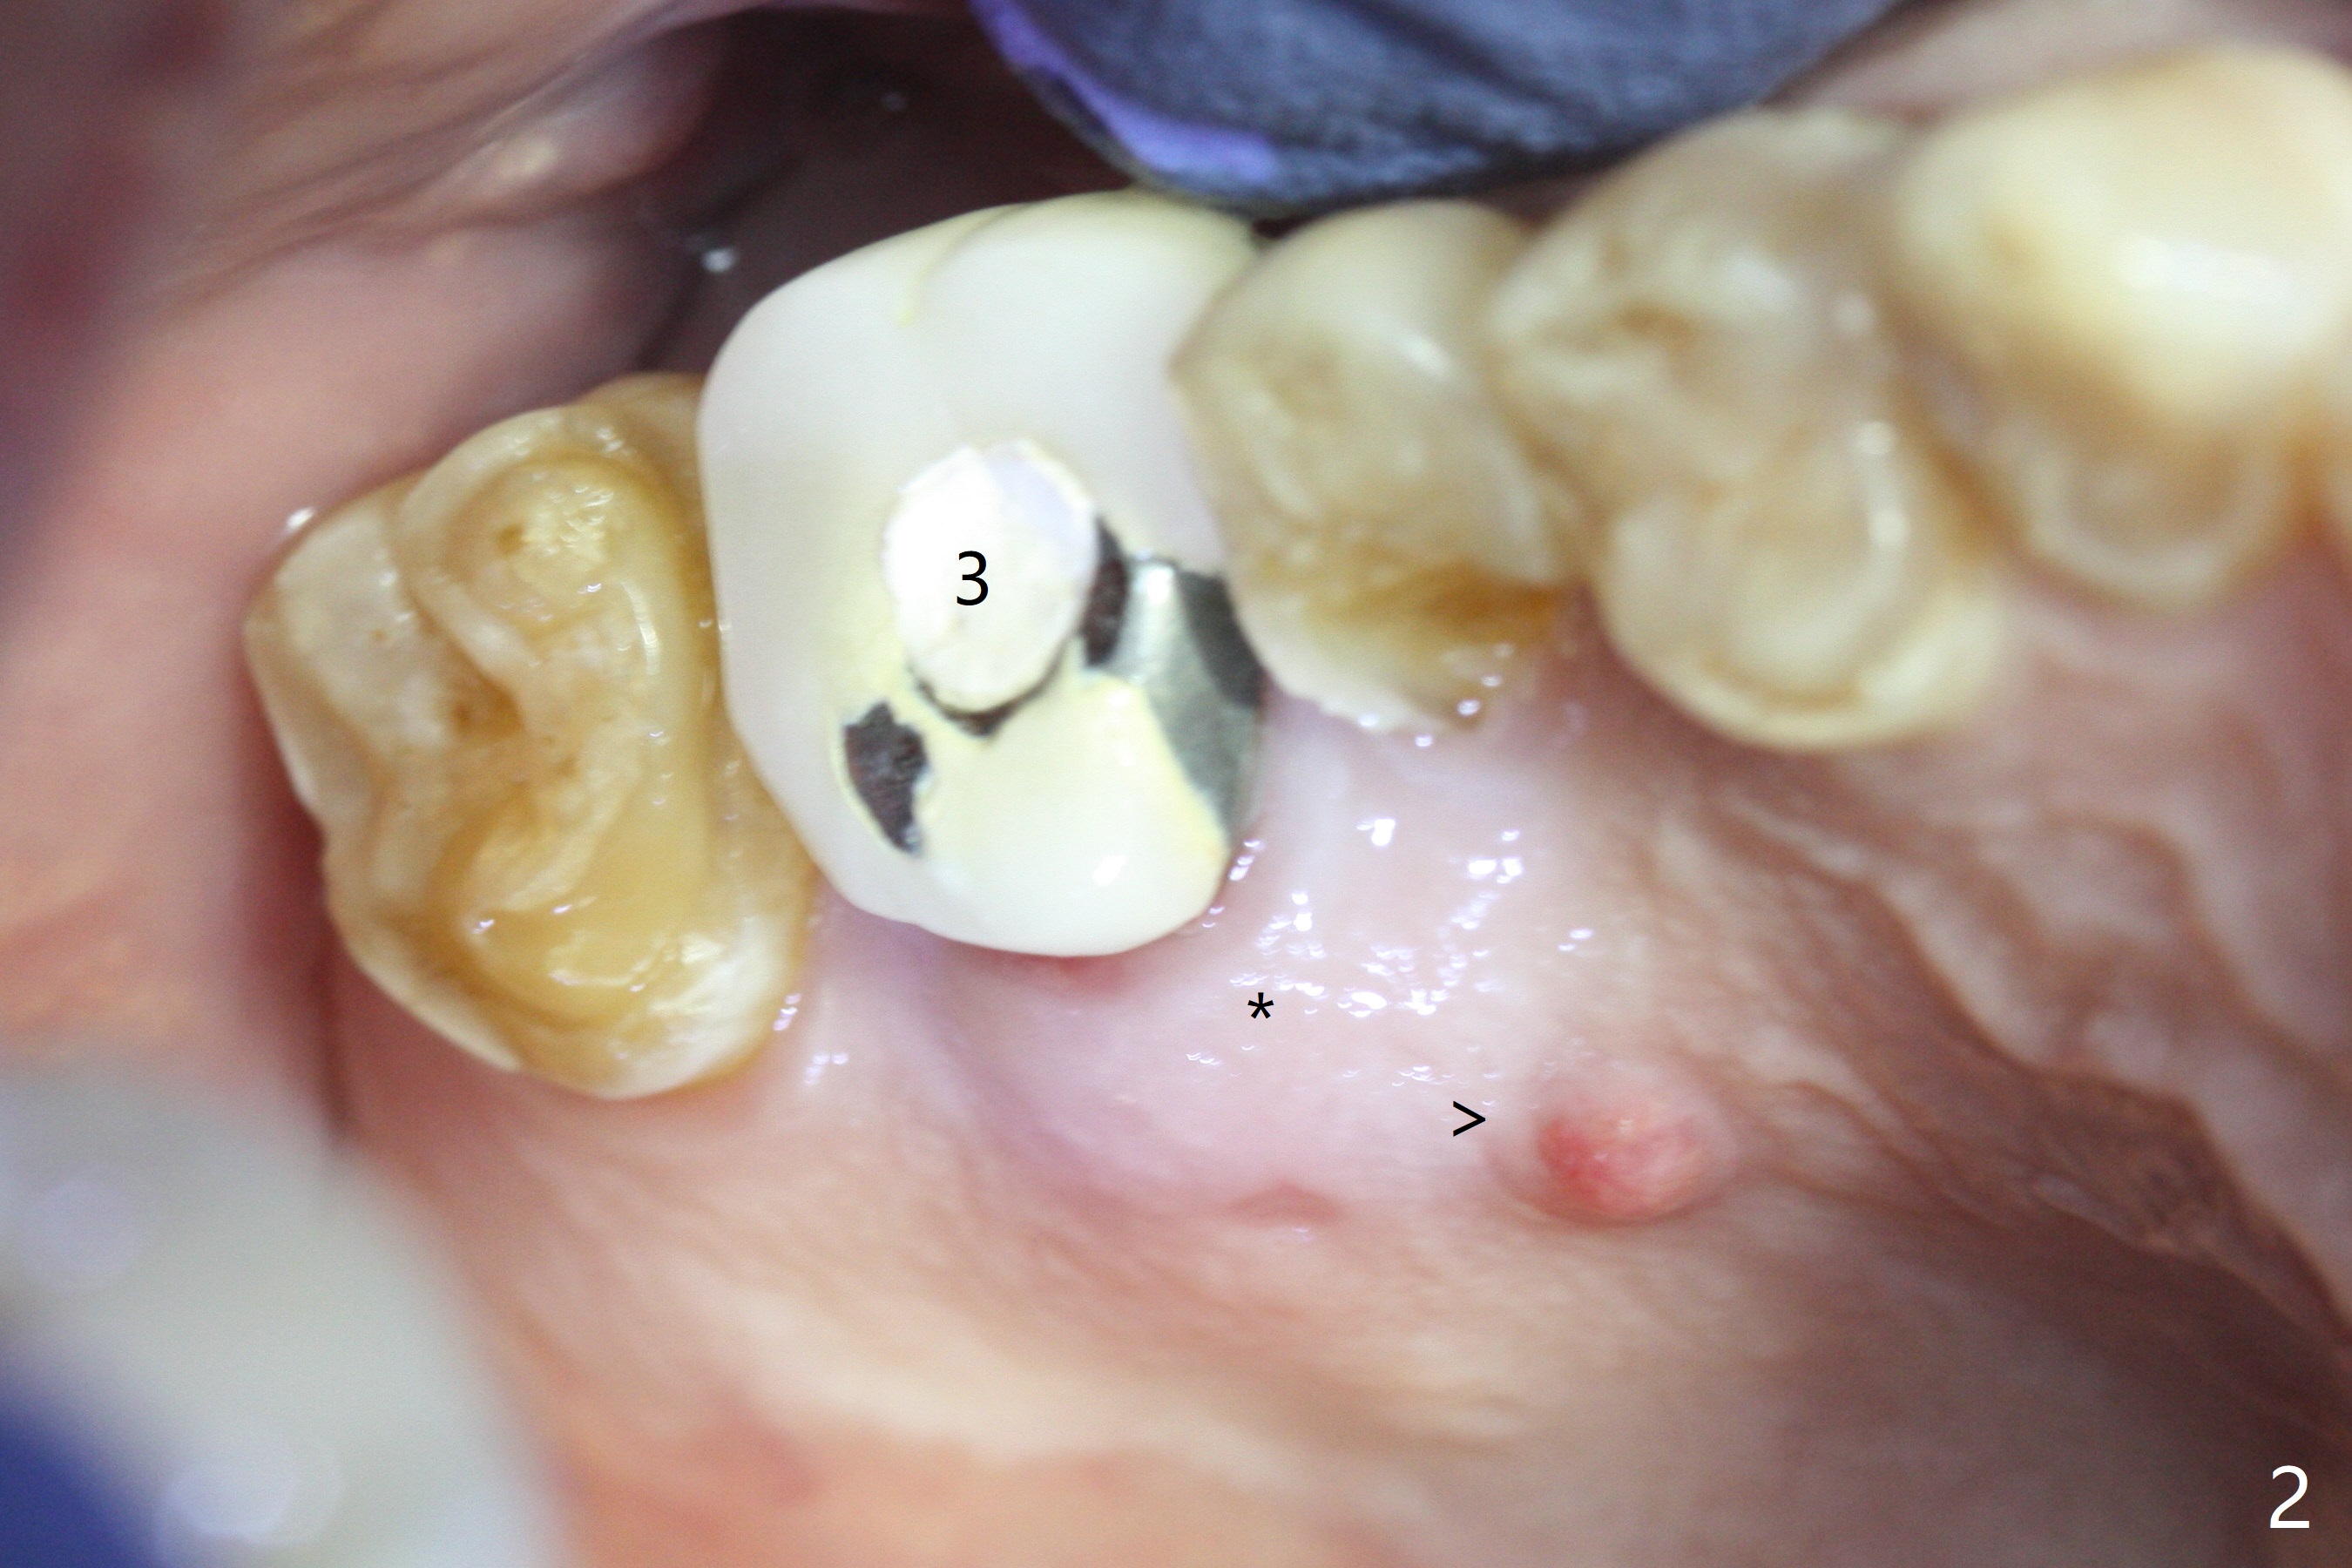

A 56-year-old man with signs of bruxism (multiple occlusal wear and tear, Fig.1) returns from an endodontist office because of failed RCT retreatment at #3 (Fig.2 (* palatal swelling; > fistula)). After difficult extraction, the socket is large without much septal bone (Fig.3 *). Because of lack of the apical native bone, immediate implant is not placed. If it has to be done, a large and long one is required. Instead socket preservation is finished (Fig.4 *). The socket is 20 mm deep, while the shank of surgical curettes is 20 mm. It appears that the most apical granulation tissue is hard to be removed. When 7-day oral Clindamycin is finished, the patient returns with chief complaint of recurrent pain and fistulae. In fact the palatal fistulae are flat without erythema. He returns asymptomatic 2 weeks postop; the fistulae are disappearing (Fig.5 ^) and the socket is healing (Fig.6).